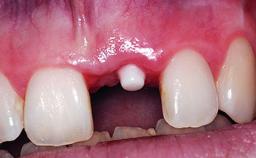

Replacement of an Upper Right Central Incisor with Root Resorption: Ridge Preservation, Delayed Placement of an NC Bone Level Roxolid Implant

Type of Implants Reduced-Diameter|Two-Piece

Placement Protocol Early or late implant placement